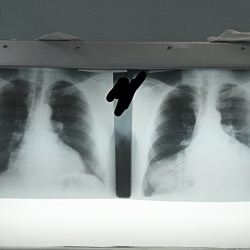

Мужчина 40 лет. Диагностическая  флюорография. Пришел на контроль, был поставлен диагноз 01.11.25 пневмония с\д, справа, в другой клинике. Смущает тень, которая видна только на задней проекции,...